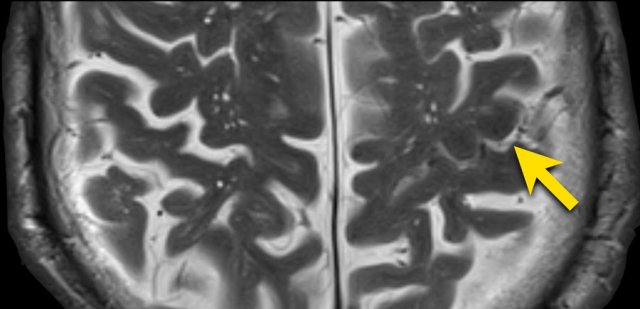

Notice how numerous these small hemorrhages are and primarily located in the perifery of the brain.

This patient presented with a cerebellar hematoma.

Continue with the T1W-image...

The T1W-image shows a hyperintense hemorrhage (arrow).